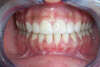

Après l'opération

En 2 séances, elle resplendit grâce à la pose de facettes collées.